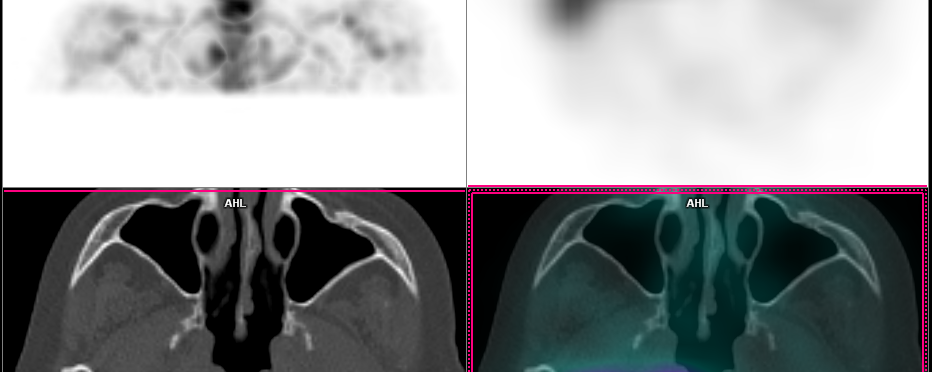

Patient de 38 ans d’origine sénégalaise (résident en Belgique depuis 10 ans) réalisant un TEP/CT 18F-FDG pour mise au point d’une masse de la surrénale gauche et d’une masse de la paroi costale antérieure droite douloureuse à la palpation.

Suspicion d’une néoplasie d’origine indéterminée avec une atteinte métastatique.

Vos impressions ?